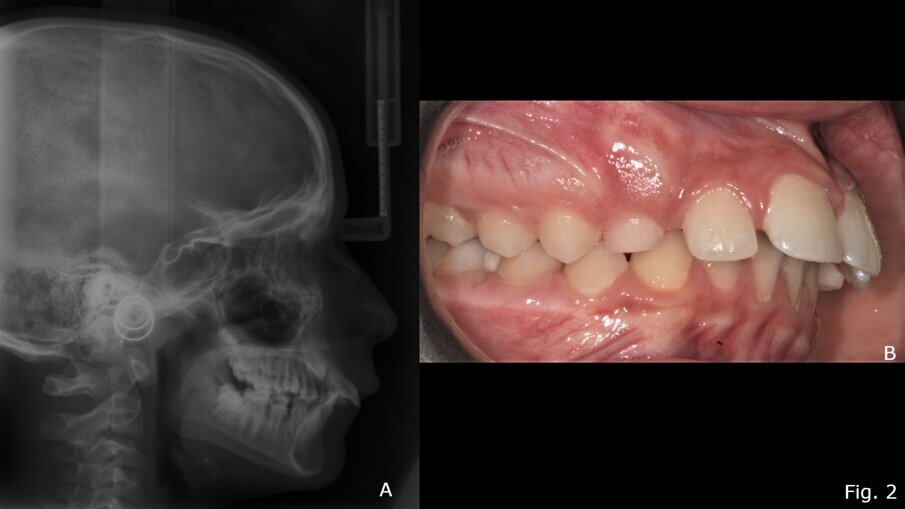

Il TB è uno dei dispositivi più comunemente usati per ottenere la correzione funzionale della malocclusione scheletrica di classe II18, 19. Provoca una riduzione statisticamente significativa dell'angolo ANB, riducendo l’OVJ e migliorando l’indice di Wits15. Il dispositivo, infatti, promuove il rimodellamento del condilo nella posizione avanzata inducendo un significativo aumento della lunghezza della mandibola (Co-Gn in mm)15, 18. Il rimodellamento adattivo può verificarsi su entrambe le superfici dell'articolazione temporo-mandibolare per migliorare la posizione della mandibola in relazione al mascellare superiore17. Un altro vantaggio è il controllo della dimensione verticale. Infatti, con il trattamento TB, lo sviluppo verticale si ottiene scartando gradualmente i blocchi in resina della placca, favorendo l'estrusione dei denti posteriori e livellando il piano occlusale20-22. Sul piano trasversale, l’utilizzo del TB ha effetti prevalentemente dentali rispetto a quelli scheletrici13. Uno degli svantaggi principali dell'apparecchio TB è che la correzione dell'overjet è data anche da cambiamenti dentoalveolari (60%) come la proclinazione degli incisivi inferiori23. Vari autori hanno proposto modifiche all'apparecchio TB per aggirare questo effetto indesiderato24-26. Ad esempio, l'uso contestuale dell'ancoraggio con mini-viti può fornire un controllo assoluto sulla posizione degli incisivi inferiori, aumentando così la correzione ortopedica nella terapia miofunzionale di classe II27. TB sembra essere particolarmente efficace nei casi di II classe in cui prevale la componente di ipoplasia mandibolare15, 28 (Figg. 2, 3).

Fig. 2 - Teleradiografia latero-laterale pre-trattamento con Twin-Block (A); Foto occlusale destra pre-trattamento (B).